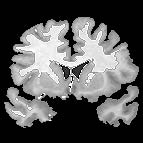

| + | |+ '''Fig 1. EM Segmentation: Cross-Sections of Segmentations (1993)''' | ||

| + | |valign="top"|[[Image:one.jpg|thumb|252px|slice of T1 weighted mr (right temporal lobe has bad "shading")]] | ||

| + | |valign="top"|[[Image:two.jpg|thumb|252px|threshoding result]] | ||

| + | |valign="top"|[[Image:three.jpg|thumb|252px|EM result]] | ||

| + | |} | ||

The EM segmenter grew out of a collaboration between Sandy Wells, Ron Kikinis and Martha Shenton in about 1993. The goal was to get good automatic segmentations of white matter and gray matter from T1 weighted MRI. The biggest difficulty was the intensity inhomogeneities, or "shading", artifact in the images that was due to the MRI scanner used for research at that time. The effect of the artifact was that a single threshold could not be used to separate white matter and gray matter.

Various approaches to the problem were tried, some giving good results, but there were remaining imperfections in the results. Eventually, we decided to construct an explicit representation of the intensity artifact, and attempt to recover the artifact and the segmentation simultaneously.

We chose the Expectation Maximization (EM) algorithm, a statistical estimation method that is used when some data is considered to be "missing". The result was an iterative algorithm that alternates between two steps.

In the "E" step, the probability of the tissue label at each voxel is estimated, given the image data and the current estimate of the intensity artifact.

In the "M" step, the intensity artifact is re-estimated, given the image data and current estimate of the tissue label probabilities.

The EM segmenter proved to be very robust to shading artifacts, but in addition, it was also robust to "inter-scan inhomogeneities". With previous classification approaches to segmentation, "training" was needed on a per-scan basis, because of intensity changes from scan to scan.

The EM segmener was the first algorithm that could produce high quality segmentations of white matter and gray matter from MRI, with no manual intervention needed on a per case basis. This proved to be very valuable in a large longitudinal study of MS in the period 1994 - 1995.